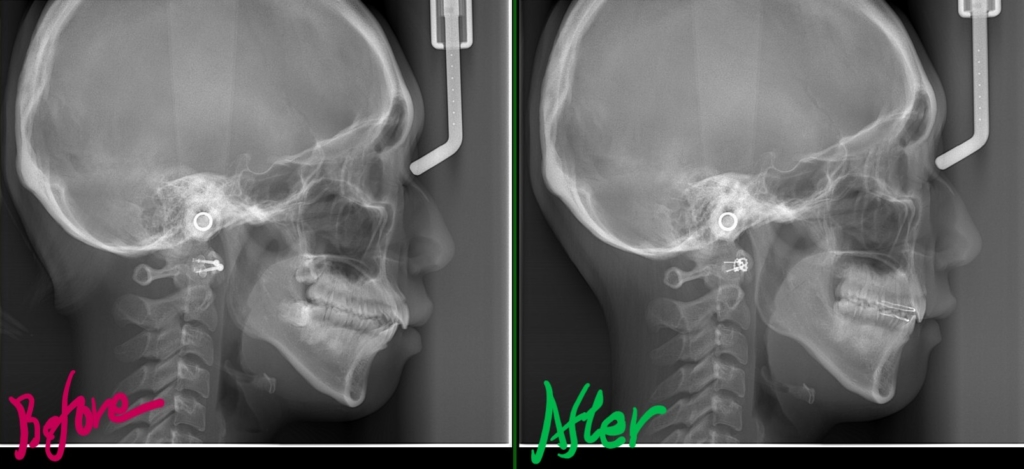

次に、レントゲン写真の比較です。

左側が矯正治療前、右側が矯正治療後

矯正後の状態をレントゲン写真で確認すると、